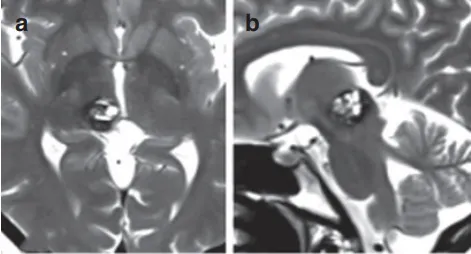

术前MRI影像显示病变情况。

导致患者左侧面部麻木、站立不稳、言语含糊的根本原因,是直径15毫米的海绵状血管瘤,病灶潜伏于大脑中心地带中脑上部与右侧丘脑之间的松果体区,该区域解剖结构极为复杂且手术风险高。